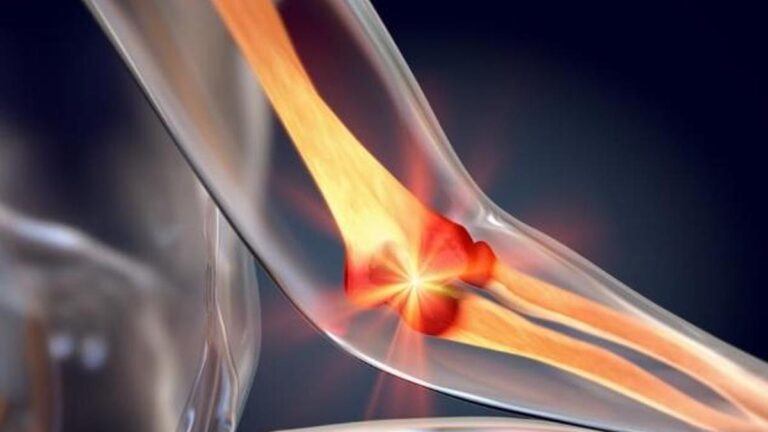

Futbol gıda veya takviyeden alınır. Kaslar, kemikler, dişler, kan pıhtılaşması ve metabolizma üzerinde büyük bir etkiye sahiptir. Vücudun farklı nedenlerle kalsiyum almasından sonra bazı hastalıklar ortaya çıkabilir. Kalsiyum eksikliğinde kemik reabsorpsiyonu, rasortizm, osteomalasya gibi hastalıklar meydana gelebilir. Aynı zamanda, bu mineralin olmaması depresyona yol açabilir.

Birçok insan futbol eksikliğini deneyebilir. Futbol esas olarak kemiklerde ve dişlerde korunur. Bu nedenle, kalsiyum eksikliği meydana geldiğinde, kemikler ve dişler ilgilenmeye başlar. Futbol eksikliğine neden olabilecek bazı durumlar var.